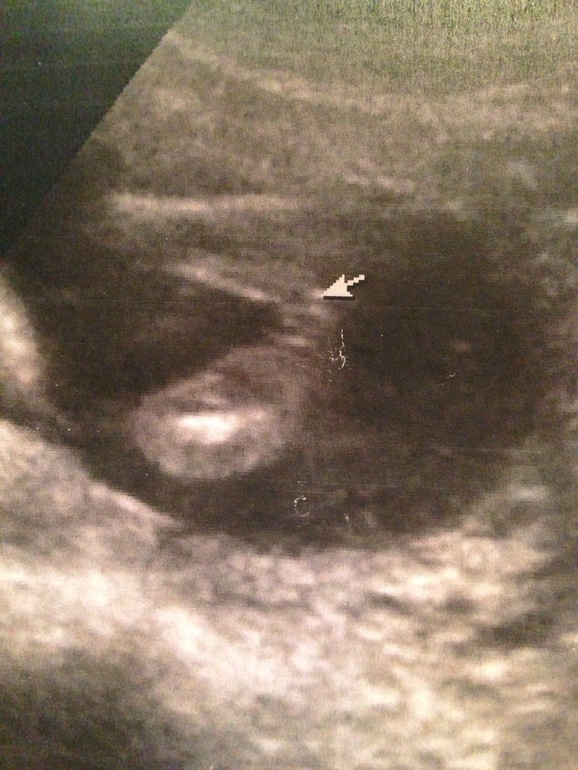

У нас наоборот, ничего не торчало , даже фото дали ( смотри выше )

По всем приметам мальчик, а вот по узи не понятно ! Хотя она нам фото дала где нет писана

В 18 недель на одном узи сказали что на мальчика похож, через пару дней - девочка !